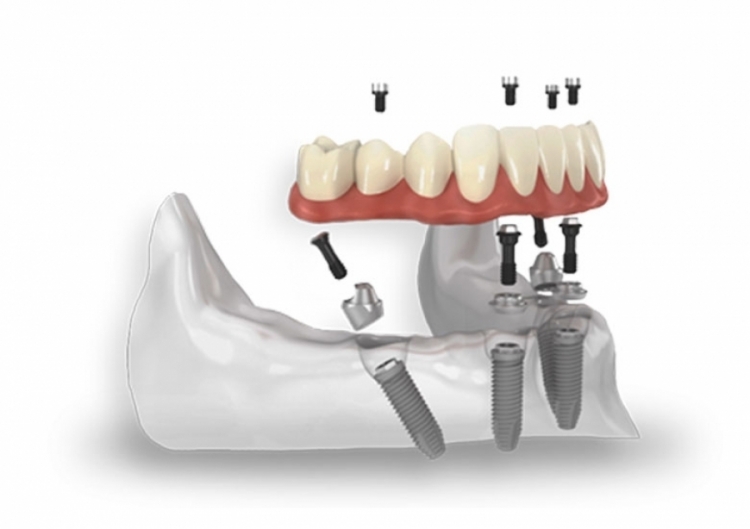

All on 4 ™ – Metodo su Quattro Impianti

Il metodo All-on-4™ consiste nella realizzazione e installazione di protesi per arcate completamente edentule, utilizzando solo 4 impianti.

È particolarmente indicato per chi desidera una soluzione fissa ma non dispone di sufficiente osso nella parte posteriore della mascella, spesso dovuto alla lunga assenza dei denti.

Il paziente riceve una protesi temporanea fissa entro 24 ore. Scopri di Più

All on 6 ™ – Metodo su Sei Impianti

Questa soluzione è ideale per chi ha perso tutti o la maggior parte dei denti di un’arcata e cerca una soluzione fissa e stabile per la loro sostituzione.

Questo approccio offre una soluzione completa e affidabile per il restauro di un’intera arcata dentale.